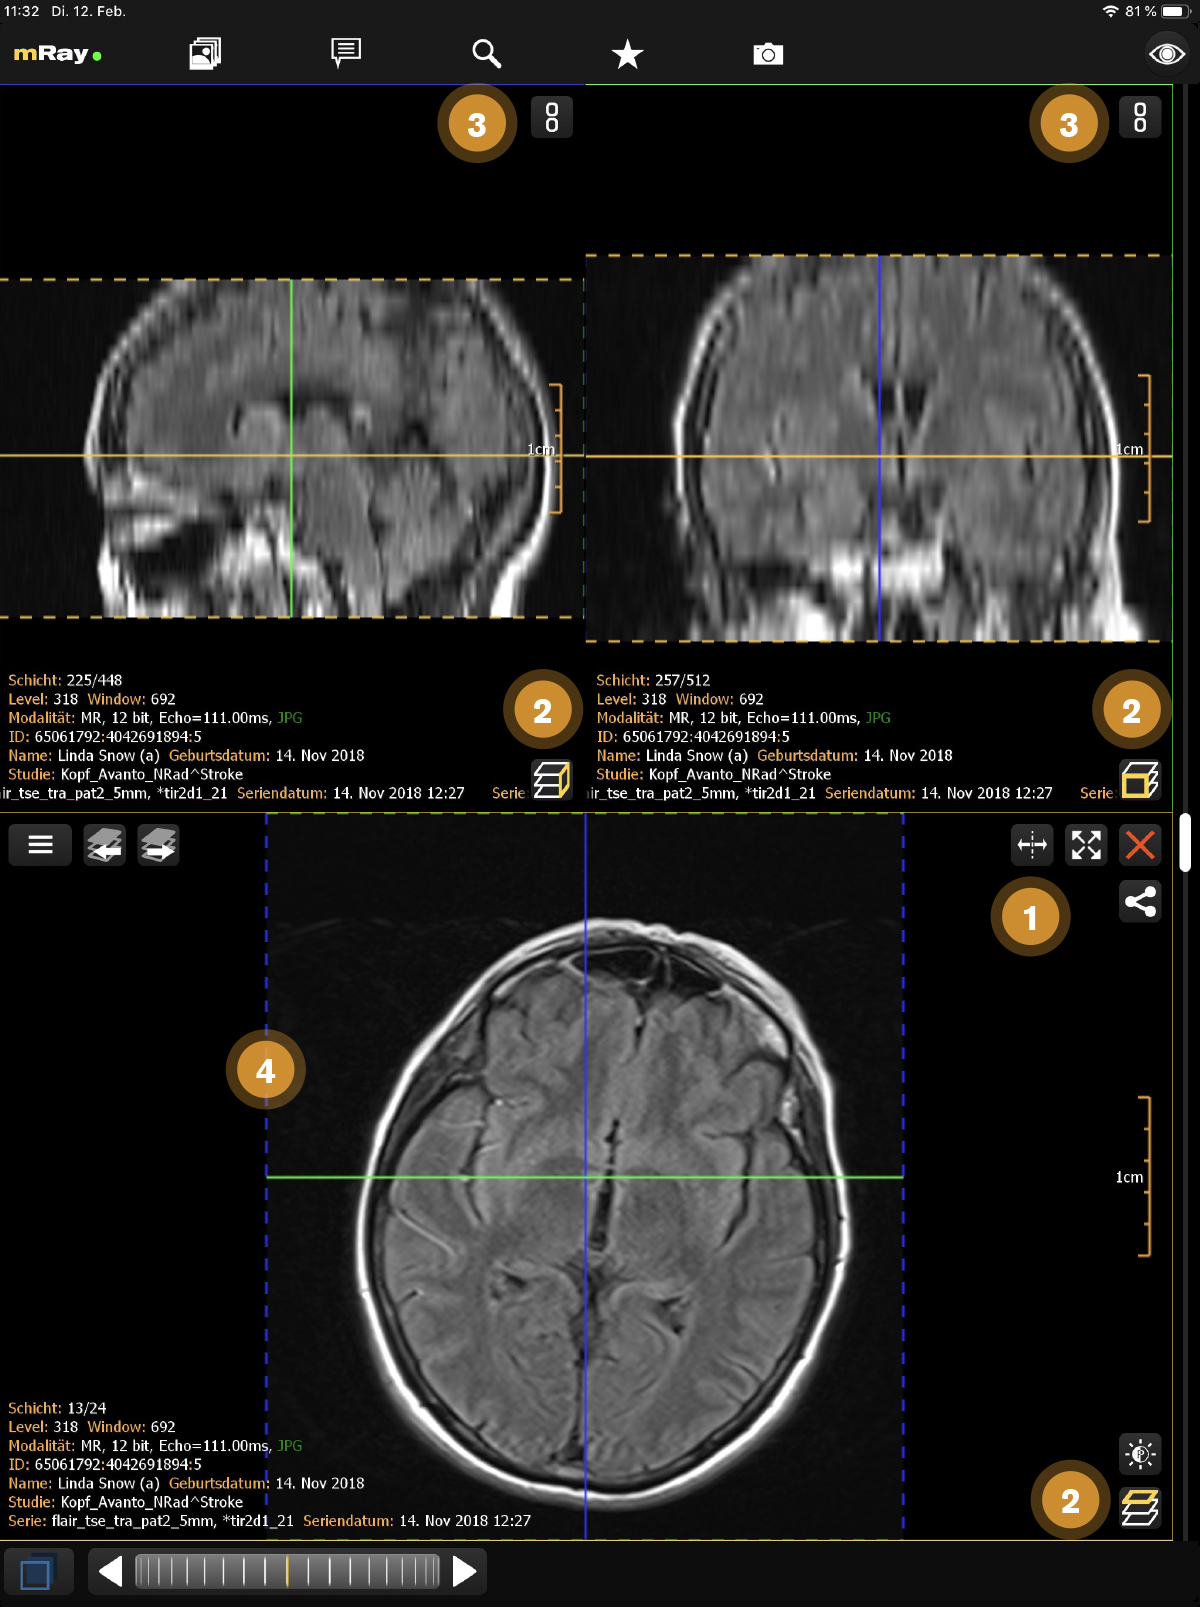

The MPR views allow you to open up multiple views at once ([abbr-mpr] View). Following screenshot shows the MPR view:

The Screenshot shows the original view of a dataset, the locally computed reconstructions (MPRs) and information to the viewed dataset.

-

Add more views here

.

The maximum number of views is 2 on smartphones and 4 on tablets.

Temporarily display view in a fullscreen state and back to previous state using maximize

.

The maximum number of views is 2 on smartphones and 4 on tablets.

Temporarily display view in a fullscreen state and back to previous state using maximize  and minimize

and minimize  icons.

icons. -

Indication of the current view direction in relation to the original image stack. You can change the view direction by pushing this button

.

. -

Use this button

to synchronize with the active view.

See Synchronized Views for more details.

to synchronize with the active view.

See Synchronized Views for more details. -

Shows the reference lines depending on the other opened views. These can be configured in the Toolmenu

You can change the perspective with the MPR perspective button (Point 2). This allows you to switch between axial, sagittal and coronal. The button in the top right corner (Point 1), allows you to open or close a view. If there is more than one view, a button to synchronize view adjustments will appear (see Synchronized Views). In order to interact with a view you have to select the appropriate view first. Therefore tap on the view. The selected view will be highlighted.